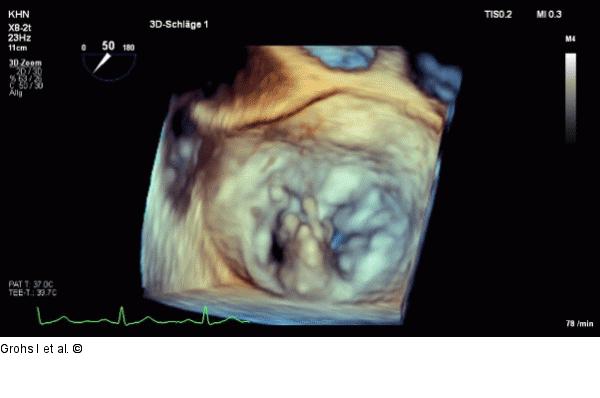

Abbildung 1: Echo-Bild Online 1 TEE, 3D en face view: Prolaps + Flail in P2 |

Abbildung 1: Echo-Bild Online 1

TEE, 3D en face view: Prolaps + Flail in P2 |